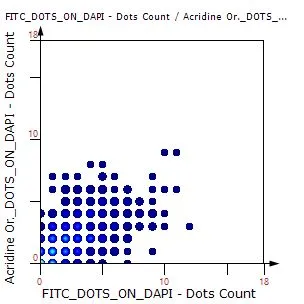

Case Study: Analysis of FISH Using Tissue Cytometry

The IF Dots App in StrataQuest streamlines automated analysis of FISH stainings by detecting nuclei and quantifying dots per cell. This case study shows how the workflow enables accurate, exportable data for genetics research and clinical applications.

Understanding the Different Types of FISH Evaluations

FISH is a powerful imaging-based technique for detecting DNA and RNA sequences directly in cells and tissues. This post explores the advantages of FISH, its complementary methods like CISH and RNAscope, and how TG solutions streamline automated FISH analysis.

How FISH Image Analysis Factors into Next-Gen Digital Pathology

How does FISH image analysis advance digital pathology? Learn how whole-slide imaging and AI-powered algorithms enable fast, accurate detection of chromosomal abnormalities, streamline workflows, and open new possibilities for precision medicine.

Quantitative Image-based Cytometry: Focus on the Foci!

Prof. Nicolas C. Hoch, University of Sao Paulo, is presenting his research on signaling and repair of DNA damage. He and his group are utilizing the power of TissueFAXS i PLUS slide scanning and the high-end image analysis solution, StrataQuest, for their research.